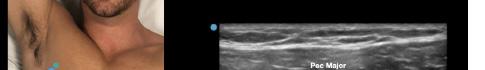

Prior to the start of the procedure, the patient must have IV access and be placed on a cardiac monitor. After informed consent has been obtained, the patient is positioned in the supine position with the head to the contralateral side of the proposed block. The physician stands at the head of the bed above the ipsilateral breast with the ultrasound screen in direct line of sight (commonly at the level of the contralateral hip). The ultrasound probe is initially placed in the sagittal plane at the midclavicular line until the clavicle, pectoralis muscles, and axillary artery and vein are visualized. The transducer is then translated caudally until the third and fourth intercostal spaces are visualized (Image 1).

At this point, the pectoralis major and minor muscles can be visualized. By rotating the transducer 45 degrees clockwise, the thoracoacromial artery can be identified between the pectoralis major and minor muscles. Also, the serratus anterior muscle should be identified resting just above the anechoic rib (Image 2).

Image 1. Initial probe placement for the pectoralis nerve block I and II illustrated on a model: the blue line indicates transducer, and the green dot indicates directional marker corresponding to ultrasound image. Image 2. Final probe placement prior to the pectoralis nerve block I and II: blue line indicates transducer, and green dot indicates directional marker corresponding to ultrasound image.